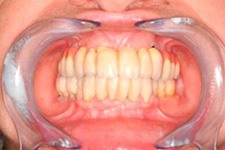

• Dokonalé obnovení funkce a estetiky

Klasickým příkladem a indikací pro použití implantátu je ztráta jednoho zubu (v tomto případě v předním – frontálním úseku) v jinak zdravém, nepoškozeném chrupu.

Náhrada jednoho zubu pomocí implantátu je možná také v postranním úseku chrupu. Při ztrátě většího počtu zubů ve frontálním nebo postranním úseku může být mezer uzavřena větším počtem jednotlivých implantátů.

S pomocí zubních implantátů můžeme díky různým kotevním systémům (třmeny, kulové hlavy, Locatory) zajistit stabilitu a držení protézy nebo při použití většího počtu implantátů zhotovit pevné náhrady – můstky nalepené nebo našroubované na pevno na implantáty.

S těmito typy náhrad můžeme dosáhnout perfektní funkci, výbornou estetiku, fonetiku a současně zajistit u pacienta možnost dobré hygienickou péče a čištění, která je pro životnost implantátů velice důležitá.